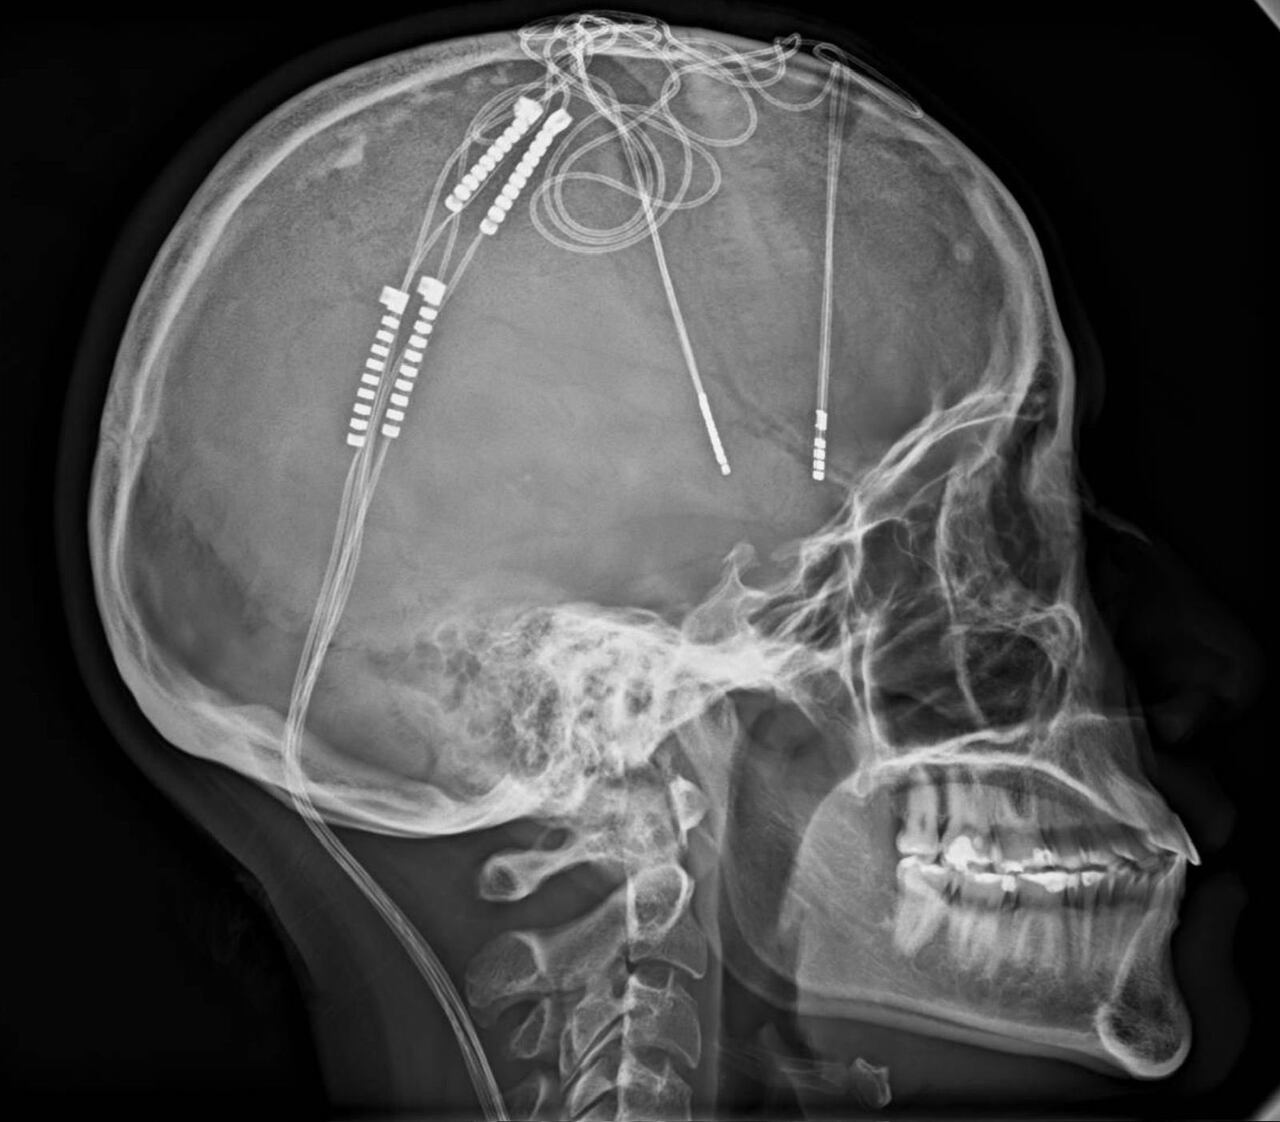

Se trata de una cirugía cerebral para mejorar esta condición en una paciente de 34 años llamada Lorena Rodríguez. Esta hazaña fue liderada por el doctor William Contreras, un neurocirujano, implantó 4 electrodos en el cerebro de la mujer con el objetivo de lograr una estimulación continua del sistema límbico, es decir, en el centro de las emociones de las personas.

Para lograr hacer el procedimiento, los profesionales introdujeron los electrodos con máxima precisión y conectaron los impulsos a una batería que se instaló debajo de la clavícula. “La batería de Lorena dura 25 años. Cuando se acabe, se reemplaza, pero los electrodos quedan de por vida”, afirmó Contreras.